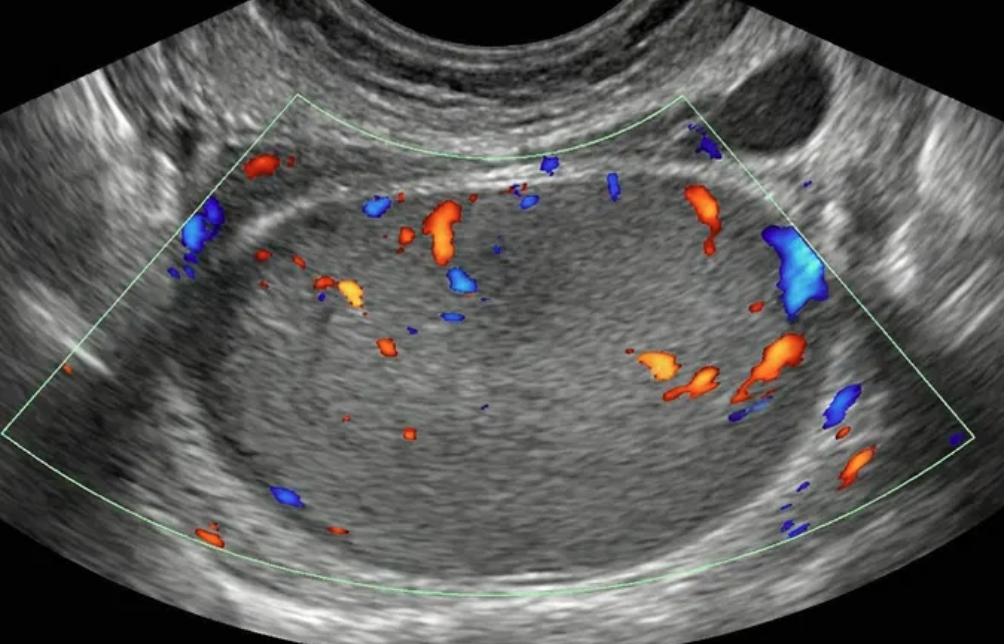

O-RADS US 5 — Alto Risco

Risco: ≥50%Cisto unilocular com ≥ 4 projeções papilares, cisto multilocular com componente sólido e IC = 3–4, lesão sólida com IC = 4 ou superfície irregular, presença de ascite e/ou nódulos peritoneais.

Achados ultrassonográficos

Conduta

Acompanhamento pelo gineco-oncologista